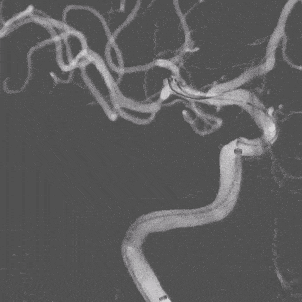

DSA结果:右侧大脑中动脉分叉部动脉瘤,大小约:2.2mmx1.7mm、瘤颈:约2.6mm,未破裂型。

术前影像